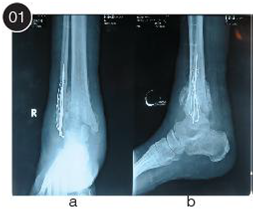

Figure 5 Final post-operative outcomes shows a well-aligned ankle arthrodesis and a plantigrade foot.